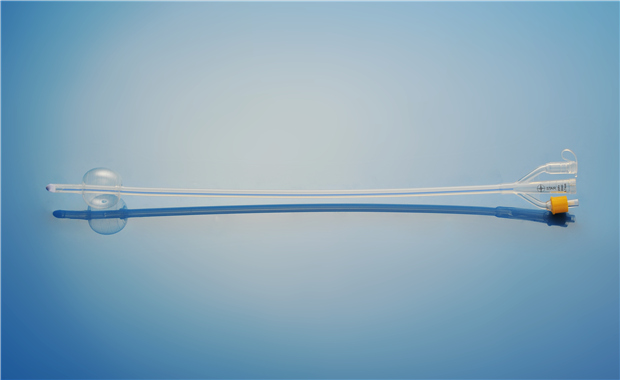

【產品名稱】一次性使用硅膠導尿管 【型號】三腔標準型 【規格】16Fr - 24Fr 【性能��、主要結構】由醫用硅橡膠為主要原材料制成���,由排泄錐形接口�����、球囊充起錐形接口等組成���。